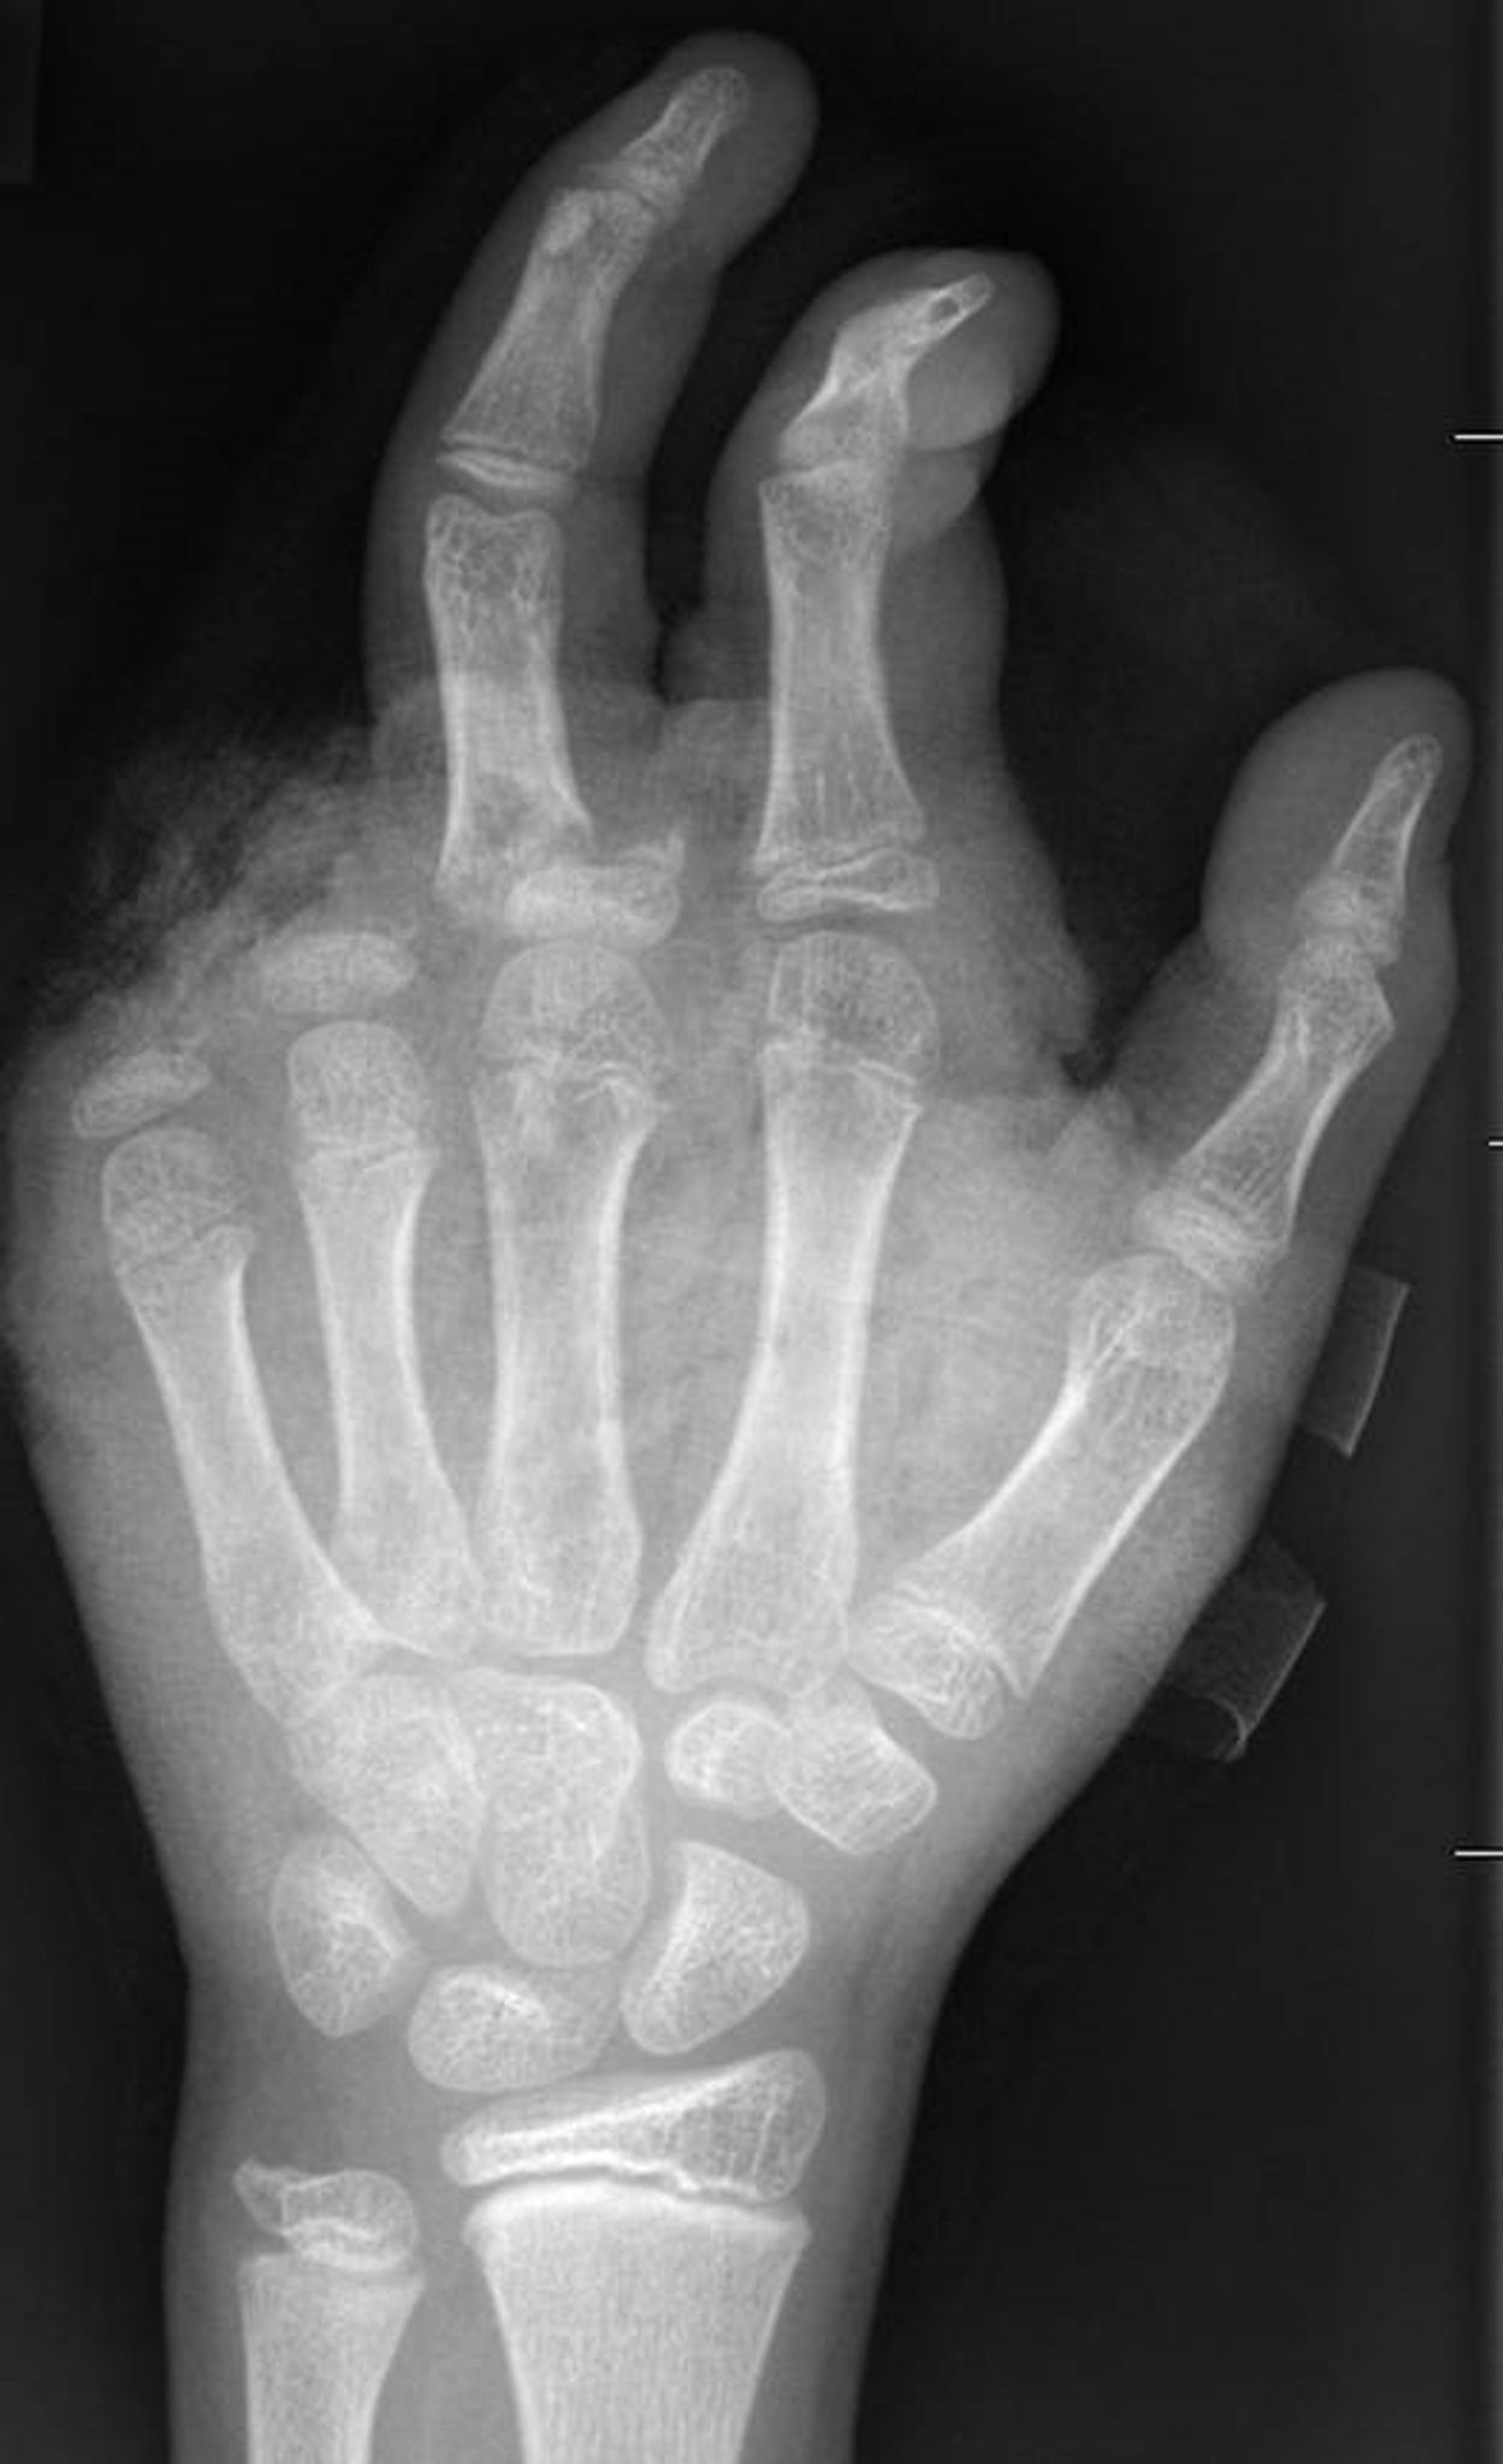

So kann ein Röntgenbild nach einer missglückten Böllerexplosion aussehen: Zwei Finger fehlen.

Copyright: -/UKB/dpa